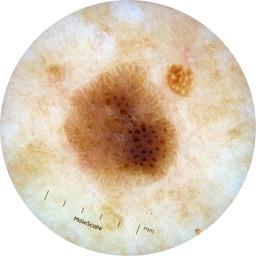

ISIC_8528385

2109 x 2109

acquisition_day 27

age_approx 60

anatom_site_1 Upper extremity

anatom_site_general upper extremity

diagnosis_1 Benign

diagnosis_confirm_type single image expert consensus

fitzpatrick_skin_type I

image_type dermoscopic